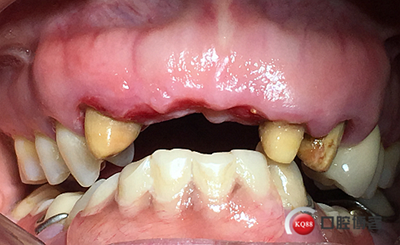

患者女性,52歲,缺失三顆牙,骨性前突,頜弓窄,身高175,魁梧,放了三顆牙是不是有點(diǎn)細(xì)?左上3開膠了,牙體有腐蝕。